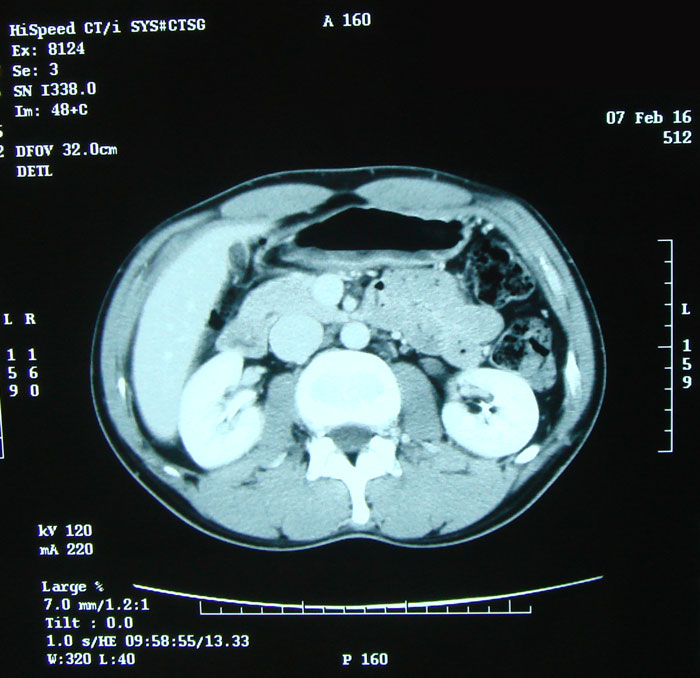

【体重/体脂肪率】

54.5kg/11.2% 2ヶ月ぶりのCT撮影。今回もくっきりな画像をと思い造影剤使用で。 造影剤の注射はすごくうまかった。痛みもほとんどなかったし針の跡も赤い点だけ。 その後、腫瘍マーカーのための採血。こちらも上手で痛みもなし。 今日は検査技師さんに恵まれたようだ。 いつもこうだといいんだけど・・・。 気になる結果は2/22。 といっても、蕎麦を食う、であるが。 ちょうど1クールの第一週が終わるころである。嘔吐ばかりしており食べることがままならない時期。この蕎麦、前職のころ毎日通っていた立ち食い。なぜか食べたくて仕方なかった。かけ220円;お好みでトッピング。安いがウマイ。 あの頃は他にも退院後にやりたいことを考えて現実逃避をしていた。ブログに書いてないことのひとつだった蕎麦は実現した。 まだまだやりたいことはある。次はなにが現実となるだろうか。楽しみだ。

53.9kg/10.5% 昼間の活動の仕方によっては体脂肪率はいとも簡単に9%台になる。 疲れやすいのは脂肪不足という話もあるしな。 担当医に「階段などがまだ辛いです。膝とかが痛くて・・・」と言ってみたところ、 カルテをぺらぺらめくって「う~~ん、、、まだ2ヶ月ちょっとだからねぇ、、、」とのお答え。 体の回復はそれだけ時間がかかるということらしい。 ゆっくり行こうぜ俺。 腫瘍マーカーも肝機能も正常値でした。 HCGΒ:0.1> GOT:29 GPT:29 来月またCT撮影を行う。

退院後最初のCT撮影。1ヵ月半ぶり。

今回も造影剤使用。はっきり写るほうがよいから希望した。 撮影中はやっぱり祈ってしまった。 何も変わってませんように! 仕事はまだ助走中な感じ。 夕方になると脚もむくみだし、お尻も痛くなってくる。 まだまだだよ、と自分に言い聞かせる事にする。 己の状態を見失うことは避けたい。 入院中は周りが皆病人。しかし今は周りはガンガン仕事をする。 人間はその環境に自分を合わせようとするらしく、しっかり自分を見つめていないと危険かも。 今がんばりすぎるのは必ずツケが来るだろうし、結果的には回りにも迷惑をかけるであろうから。 自分が頭で思っているほど元気ではないようである。 たぶん、そんなもんである。